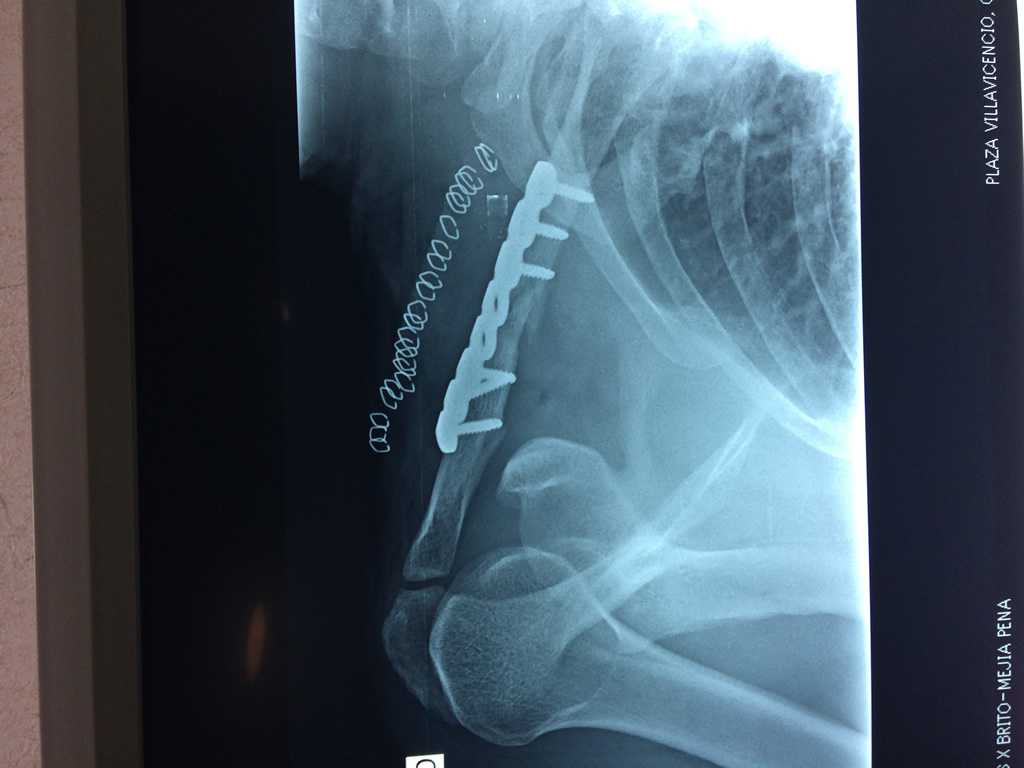

Cirugías de Húmero - Clavícula

La clavícula es un hueso largo, con forma de "S" itálica, situado en la parte anterosuperior del tórax. Junto con la escápula forman la cintura escapular. Se puede palpar por toda su longitud y se extiende del esternón al acromion de la escápula, siguiendo una dirección oblicua lateral y posterior.

Se considera el único medio de unión entre el miembro superior y el tórax. A pesar de su aspecto, similar al de un hueso largo, posee una estructura semejante a la de un hueso plano, ya que carece de epífisis y de diáfisis, lo que la harían entrar dentro de la clasificación de hueso largo. Carece de un canal medular propiamente dicho.